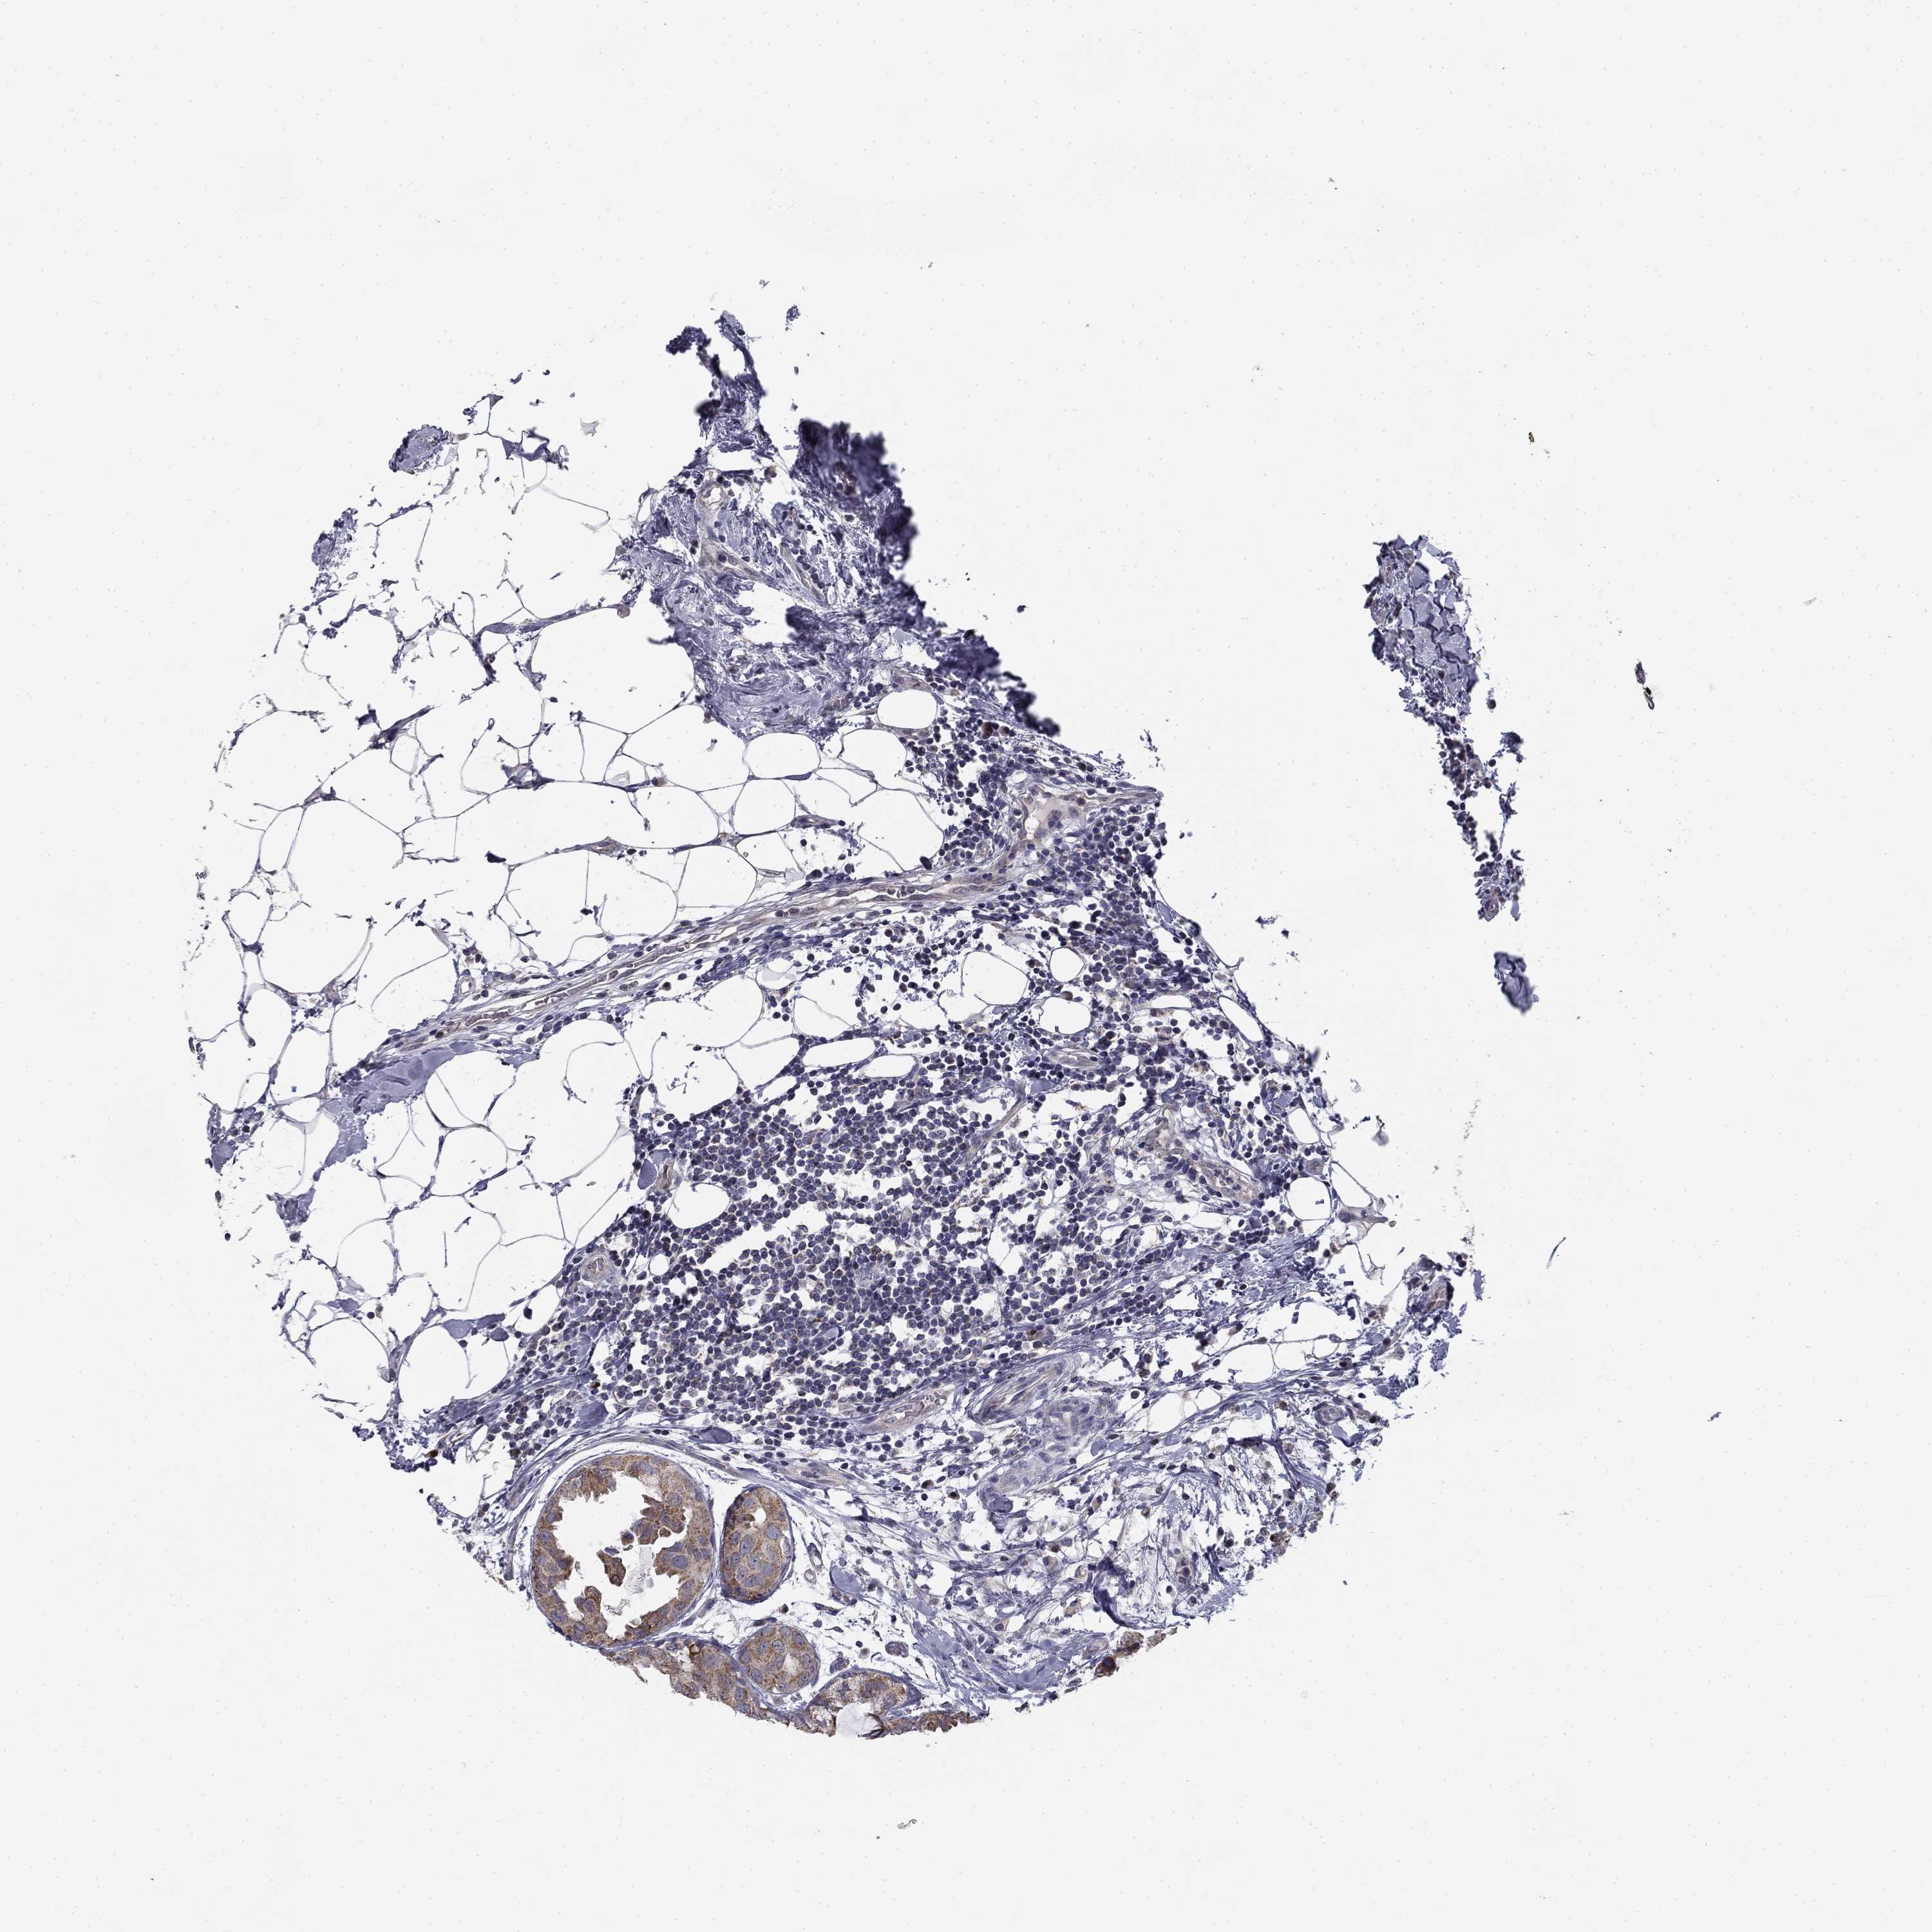

CANCER BREAST CANCER Show tissue menu

BRCA TCGA BRCA VALIDATION PROTEIN EXPRESSION

Breast cancer

Human cancer